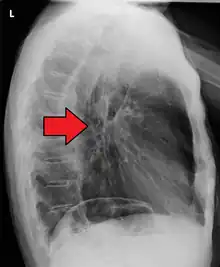

Although an occlusive tumor may be suspected on a barium swallow or barium meal, the diagnosis is best made with an examination using an endoscope. This involves the passing of a flexible tube with a light and camera down the esophagus and examining the wall, and is called an esophagogastroduodenoscopy. Biopsies taken of suspicious lesions are then examined histologically for signs of malignancy.

Additional testing is needed to assess how much the cancer has spread (see § Staging, below). Computed tomography (CT) of the chest, abdomen and pelvis can evaluate whether the cancer has spread to adjacent tissues or distant organs (especially liver and lymph nodes). The sensitivity of a CT scan is limited by its ability to detect masses (e.g. enlarged lymph nodes or involved organs) generally larger than 1 cm.[44][45] Positron emission tomography is also used to estimate the extent of the disease and is regarded as more precise than CT alone.[46] PET/MR as a novel modality has shown promising results in preoperative staging with fair feasibility and good correlation in comparison to PET/CT. It can enhance tissue differentiation with lowering the radiation dose to the patient.[47] Esophageal endoscopic ultrasound can provide staging information regarding the level of tumor invasion, and possible spread to regional lymph nodes.

Endoscopy and radial endoscopic ultrasound images of a submucosal tumor in the central portion of the esophagus- Contrast CT scan showing an esophageal tumor (axial view)